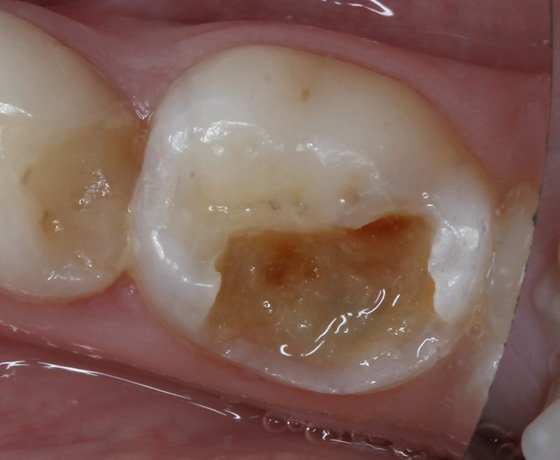

Post treatment situation immediately after petroleum jelly removal.